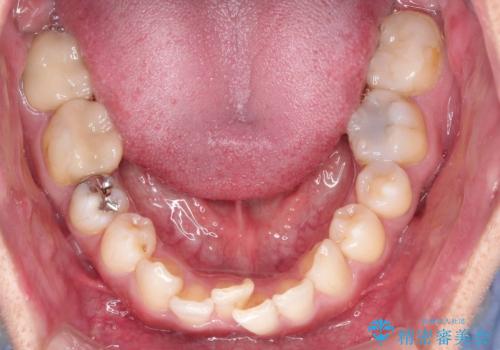

【インビザライン】八重歯と歯のでこぼこが気になる!

- 「八重歯と歯のでこぼこを治したい」を主訴に来院された患者様です。

歯は抜かずに奥歯の遠心移動とIPRで八重歯とでこぼこを改善しました。